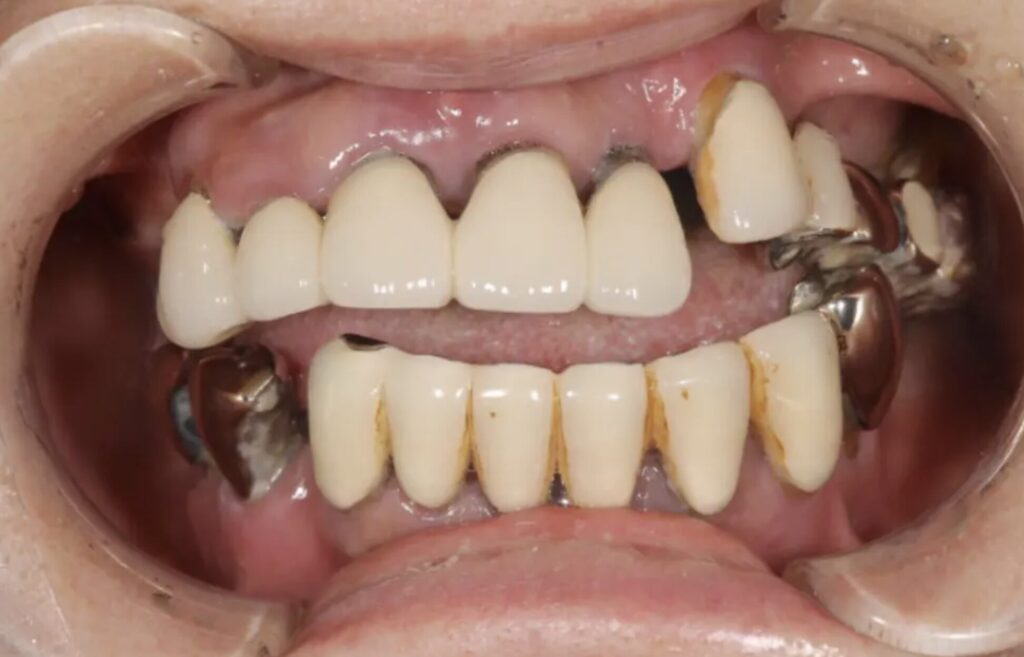

「入れ歯では噛めない」からの解放|インプラントオーバーデンチャーで劇的改善した症例

| 年代・性別 | 60代女性 |

| 主訴 | 左上のブリッジが外れかけている、歯がないところに歯を入れたい |

| 診断 | 病的咬合 |

| 治療内容 | 上:金属床下:インプラントオーバーデンチャー |

| 費用 | 約200万(税込) |

| 期間 | 1年半 |

| リスク・副作用 | 外科処置が必要。入れ歯で噛みにくい期間がある。静脈内鎮静における注意事項がある |

60代女性の患者様は、「左上のブリッジが外れかけている」「歯がないところに歯を入れたい」というお悩みで来院されました。長年ご両親の介護を優先し、自分の歯の治療を後回しにされていたそうです。これまで入れ歯での生活に不自由を感じていたことから、しっかり噛める治療を希望。診断の結果、上顎は総義歯、下顎はインプラントオーバーデンチャーで治療を行いました。静脈内鎮静下でのオペにより、恐怖や痛みを抑えながら、安全に手術を実施。治療後は噛み心地・見た目ともに大きく改善し、入れ歯では得られなかった安定感と自信を取り戻された症例です。